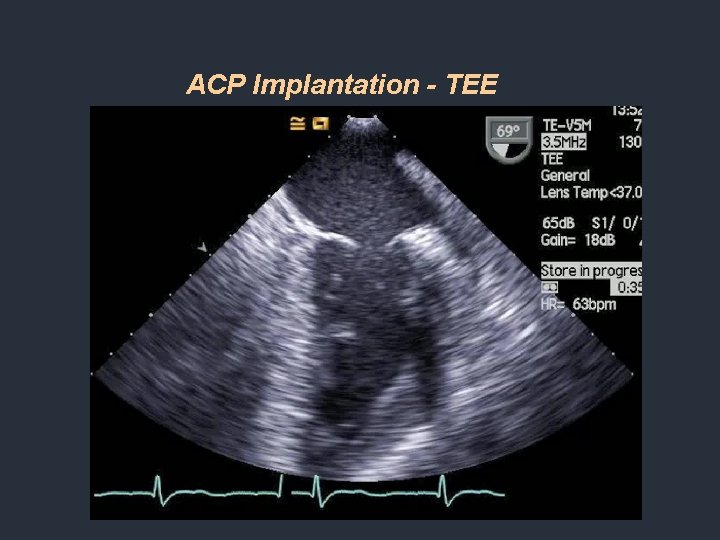

ACP Implantation - TEE

AMPLATZER® Cardiac Plug Device Description Transcatheter self-expanding device intended for use in preventing thrombus embolization from the left atrial appendage Delivery System Torq. Vue® 45° x 45° Delivery Sheath: 9, 10 and 13 Fr. Sizes Device Size Eight sizes: 16 – 30 mm in 2 mm increment; Disc Dia. 4 or 6 mm > Lobe Dia. ; Covering 18 – 28 mm LAA Orifice Product Approval and Indication CE Mark since Q 4 2008 U. S. Clinical Feasibility Trial Q 2 2010